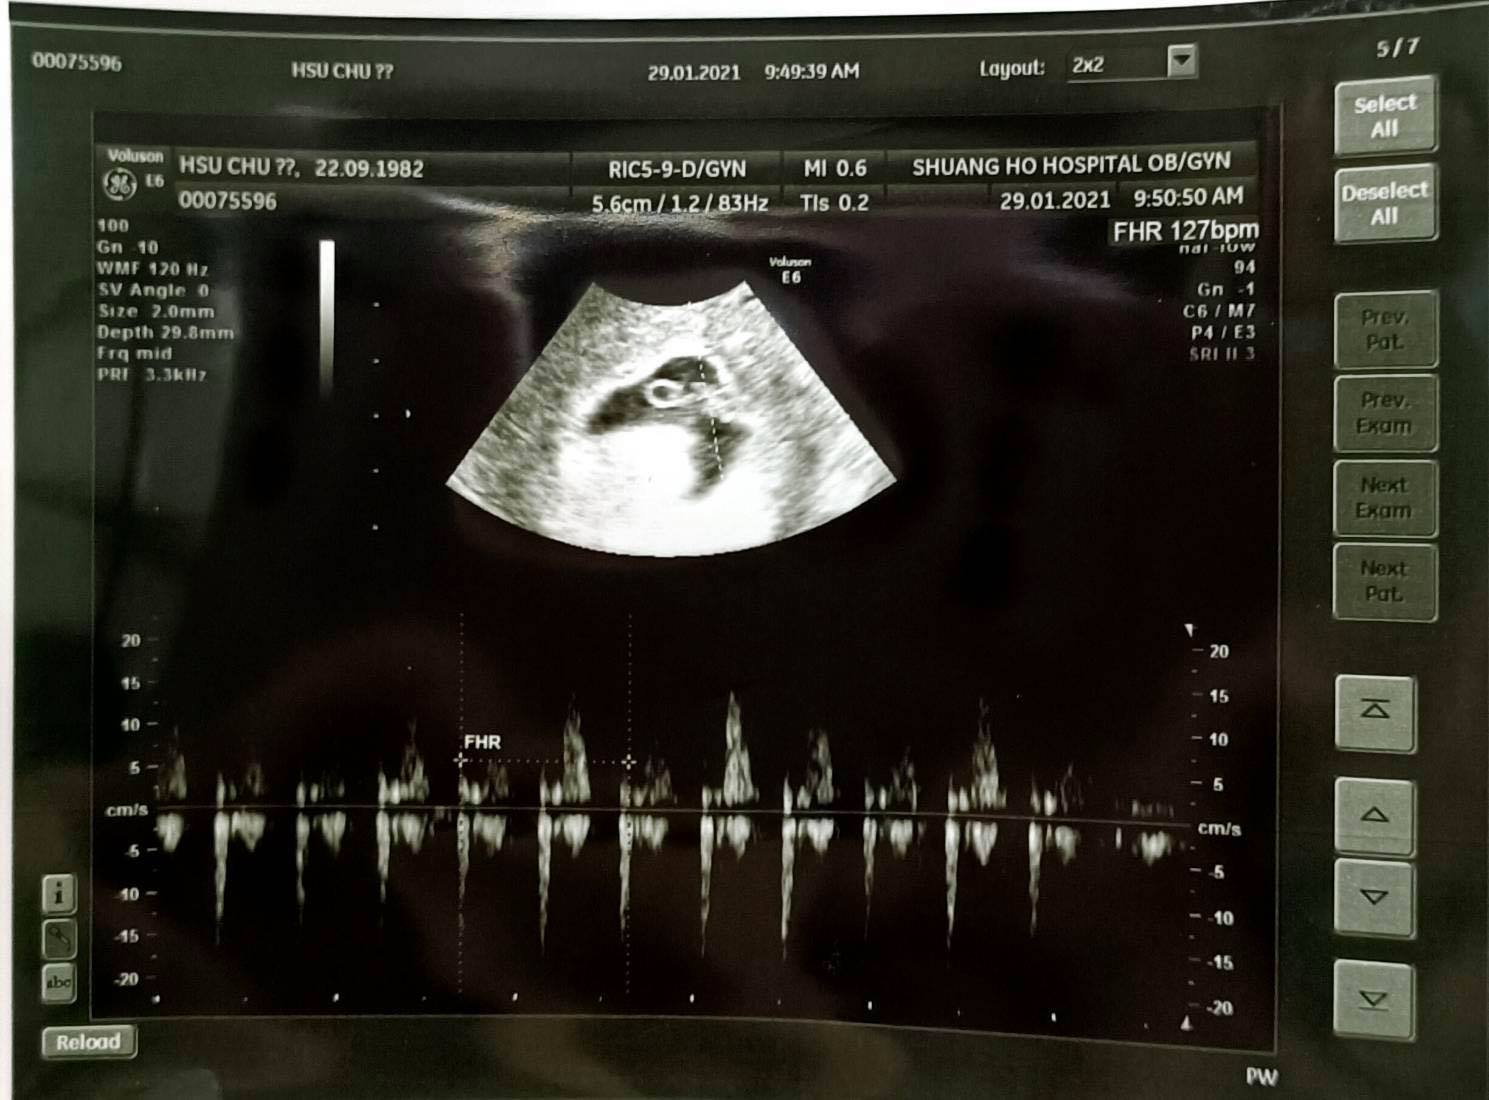

終於確定看到小寶貝的胚胎與心跳

真是替她恭喜萬分